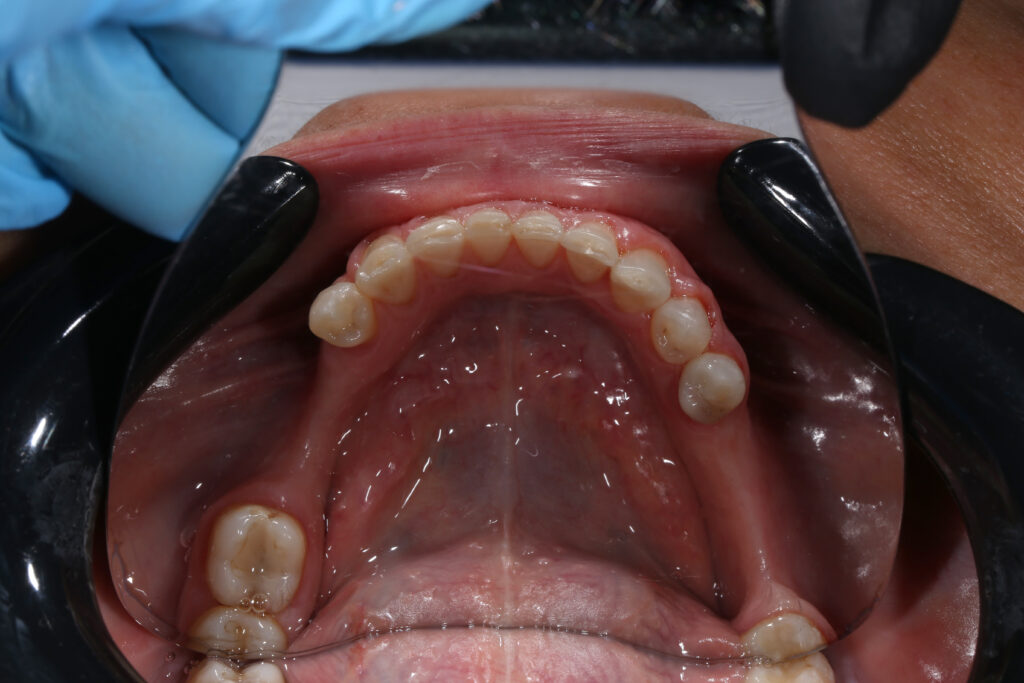

Ситуация до лечения

Пациентка 39 лет была направлена стоматологом-ортопедом для ортодонтической подготовки перед протезированием.

Из-за множественных давних удалений жевательных зубов, произошла деформация зубных рядов, зубы разъехались в область удаленных, что затрудняло протезирование в момент обращения к ортопеду.

Так же можно отметить сильное снижение высоты прикуса (верхние зубы на 100% перекрывали нижние, что вызывало хроническую травму десны), а также повышенную стираемость твердых тканей зубов,

что является следствием повышенной нагрузки, которую много лет испытывали передние зубы, в связи с отсутствием жевательных зубов.

пациент до брекетов